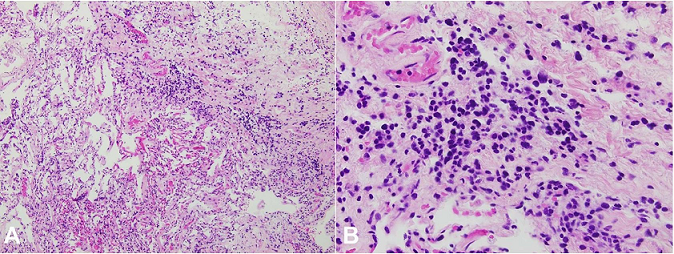

Microscopic examination of the heart, kidneys, perinephric fat and lungs, demonstrated an infiltrate of large, pleomorphic lymphocytes with scattered associated apoptotic debris ( Figures 3- 5). The liver, adrenal glands and periadrenal fat, and a small bowel plaque were also involved by this same infiltrate ( Figure 6).

While areas suggestive of a cellular infiltrate were identified in the spleen, particularly in a perivascular location, the organ was markedly autolyzed, precluding definitive histomorphologic assessment. In the affected tissues, the infiltrating lymphocytes disrupted and focally effaced the normal architecture. There were no germinal centers or follicles appreciated, and overall, the cells were dyscohesive. Of note, variable autolysis affected all sampled tissues. The bone marrow was found to be hypercellular for age, although no definitive areas of cellular infiltrate were identified.

Discernible morphologic features of the infiltrates in all affected organs included the previously mentioned large size, round to oval nuclei with irregular contours, and high nuclear to cytoplasmic ratio. Nucleoli were present in a majority of the neoplastic cells. The findings on hematoxylin- and eosin-stained sections were suggestive of a diffusely infiltrative neoplastic process with intermediate to high grade nuclei, and immunohistochemical stains were performed to further characterize the lymphoid infiltrate. Negative staining for CD3 (T-cell marker) and positive staining for CD20 (B-cell marker) confirmed B-cell lineage ( Figure 7A and 7B). Kappa and Lambda were both negative in the neoplastic cells. A Ki-67 stain was weakly positive in over 50% of the cells of interest ( Figure 7C).